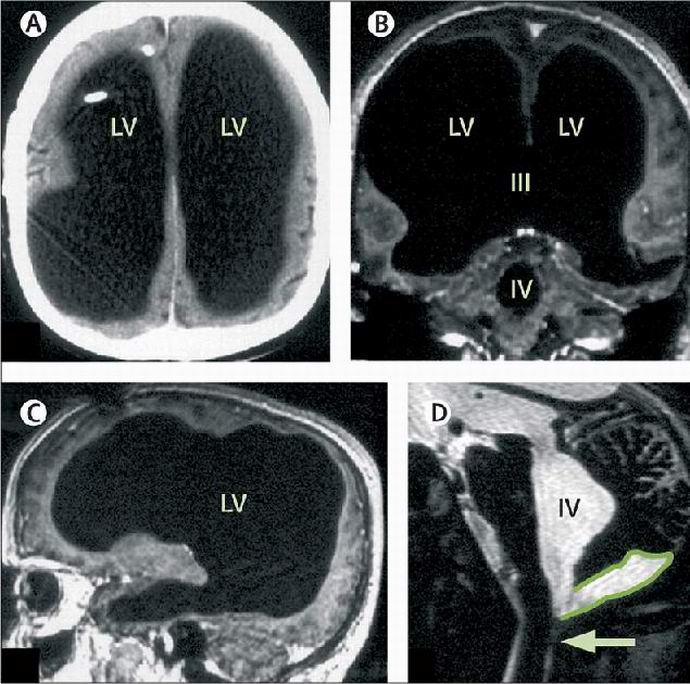

Kun lääkärit saavuttivat Mathieun aivotutkimuksen, he osoittautuivat kirjaimellisesti järkyttynyt. Miehen aivot olivat niin pienet että kuvissa sitä ei käytännössä ollut havaittavissa. Sarjan jälkeen testit, lääkärit totesivat, että aivo-selkäydinneste, kiertää terveellä henkilöllä aivoissa ja erittyy sisään verenkiertoelimistö, täytti potilaan kallon, poistuen erittäin pieni määrä harmaata ainetta. Struck tämän löytöasiantuntijat alkoivat ymmärtää ilmiön luonnetta ja havaitsi, että lapsuudessa miestä hoidettiin vesisuonen – muun vuoksi sanoin, hänet pumpattiin aivojen ylimääräisestä nesteestä. Tätä varten lääkärit Mathieulla oli šunti, ja sitten hän poisti šuntin. Mutta kuten nähdään, ongelma sen jälkeen ei kadonnut.

Puoli vuosisataa ylimääräinen neste on kertynyt kallon sisään Ranskalaisen laatikko ja syrjäytti aivonsa. Hämmästyttävä, mutta kipu jaloissa tuli ensimmäiseksi ja toistaiseksi ainoaksi komplikaatioksi, joka liittyi hänen tauti. Kahdeksan viime vuoden ajan tutkijat ovat tutkineet vartaloa huolellisesti. Mathieu. Hänen aivojensa pienten kokojen oletetaan olevan vesisuuntauksen seurauksena siitä, kuinka ihminen asui hiljaa kaikki nämä vuodet ovat todellinen mysteeri.